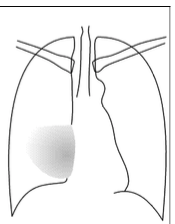

what does this show

RML collapse